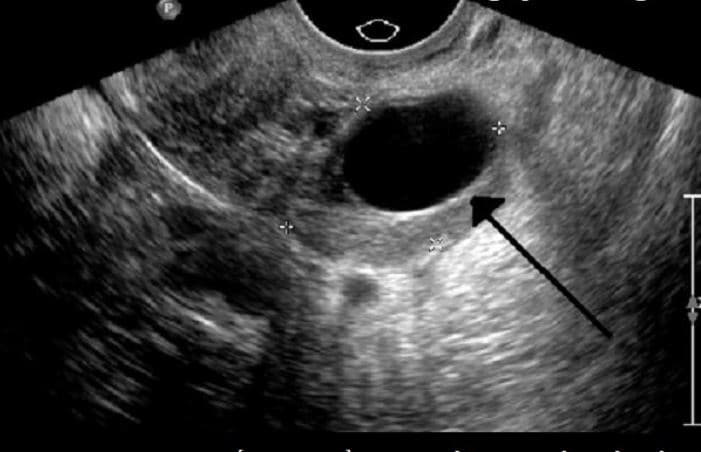

Hình ảnh siêu âm của một trường hợp không có phôi thai

Ban đầu, trứng rỗng sẽ tiếp tục phát triển về kích thước. Tuy nhiên từ tuần thai 8 – 13, trứng rỗng này sẽ bị đào thải và gây nên tình trạng sảy thai. Sảy thai được xem như sự tự đào thải của cơ thể đối với các trứng thụ tinh có những bất thường.